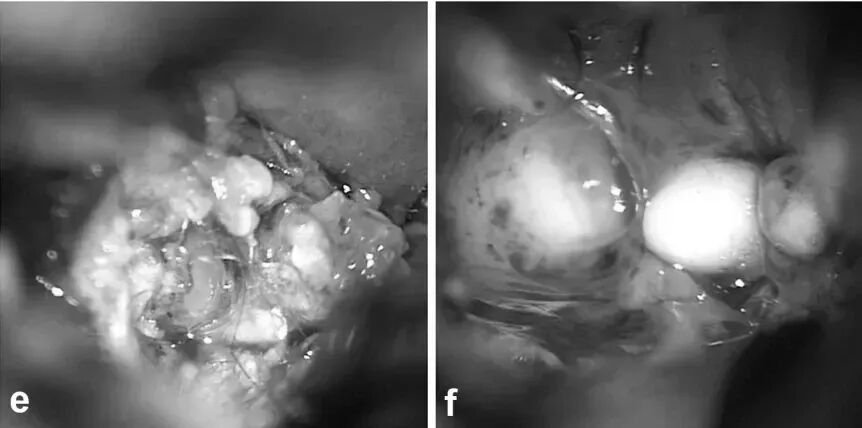

03. 手术全切与长期康复结局